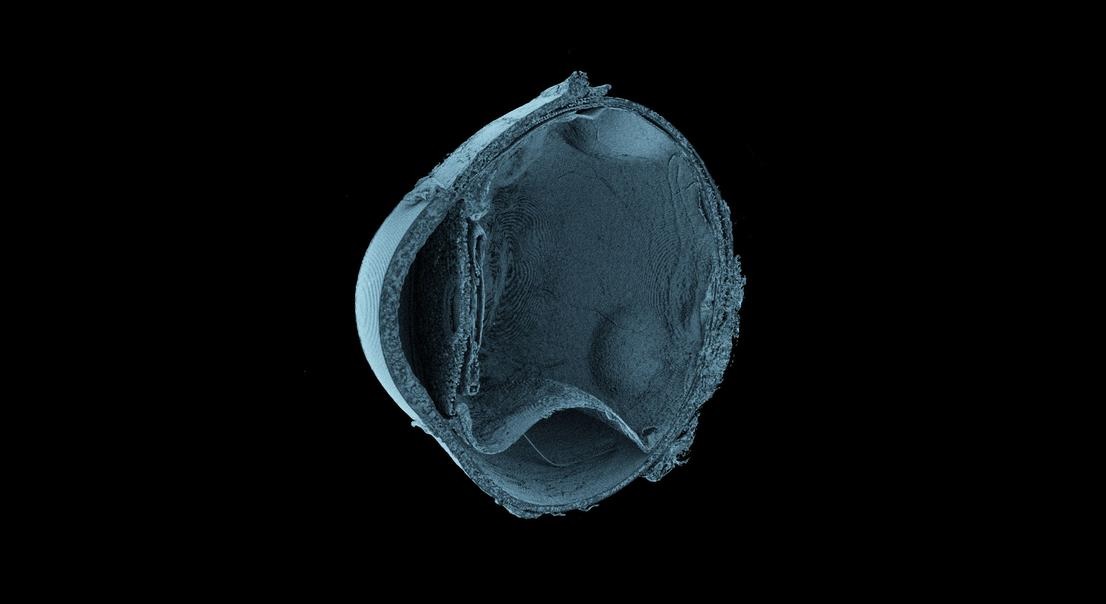

Entre los logros destacados del proyecto se encuentra el escaneo completo en 3D de un colon humano con una resolución cercana a la escala celular, un hito sin precedentes en la historia de la imagen biomédica. Asimismo, el atlas ha capturado órganos como el corazón desde múltiples perspectivas, revelando su organización interna con una precisión inédita, lo que abre nuevas vías para la comprensión de su funcionamiento y de las patologías que lo afectan.

Gracias a esta capacidad, los investigadores pueden escanear órganos humanos intactos en condiciones ex vivo sin provocar daños en su estructura, y posteriormente ampliar las imágenes hasta alcanzar resoluciones inferiores a una micra, aproximadamente cincuenta veces más finas que el grosor de un cabello humano. Esta característica permite observar detalles microscópicos dentro de órganos completos, superando las limitaciones tradicionales de las técnicas de imagen médica.

Los responsables del proyecto sostienen que esta tecnología permite cerrar una brecha histórica en medicina entre la radiología y la histología, al combinar la visión integral del órgano con el análisis microscópico de sus tejidos. En el artículo científico publicado en la revista Science Advances, los autores señalan que el método ofrece “una exploración integral de la anatomía humana, proporcionando una perspectiva inigualable de las estructuras complejas y sus relaciones espaciales”.